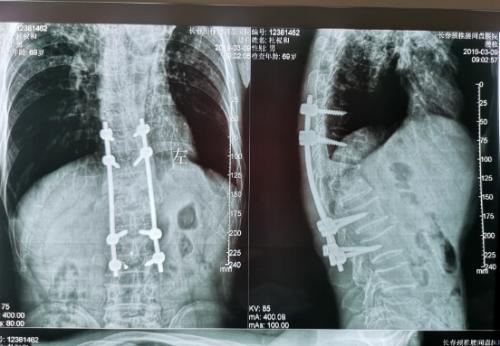

经过检查,罗坚主任凭着丰富的临床经验初步认为王大爷患的是胸椎结核伴脊髓压迫症,那么是什么原因导致的?通过脊柱磁共振检查,罗主任发现王大爷患胸椎脊髓压迫的元凶正是“骨结核”。王大爷胸椎骨7-11节被结核杆菌严重侵蚀,在重体力活后,胸椎脊髓神经受到压迫,最终导致下肢瘫痪。同时患者双肺结核伴左上叶不张,左侧胸腔大量积液。如果等待双肺结核治愈,需时日很长,脊髓的受压如果不能及时解除,导致脊髓变性,那么瘫痪就难以恢复了,在积极治疗肺结核胸腔积液引流,罗坚主任为王大爷尽快安排实施手术。

手术过程中,病人腰大肌脓肿巨大,病椎破坏重游离死骨多,结核物质使脊髓严重受压,既要侧前方减压清除病灶,又要完成后凸畸形的矫正,再由于王大爷年龄较大、体质差,风险高,对技术与手术期管理都是很大的挑战。

罗坚、陈松峰和任重三位医师组成的团队实施手术。罗坚主任凭借其多年外科生涯中大量胸椎结核手术所积累的丰富经验,在脊柱侧前方减压,病灶清除、植骨和后凸畸形矫正胸膜外操作。手术按计划顺利完成,而辗转数家医院的“求医记”终于告一段落,在外等候的家人听到手术成功的消息后喜极而泣。